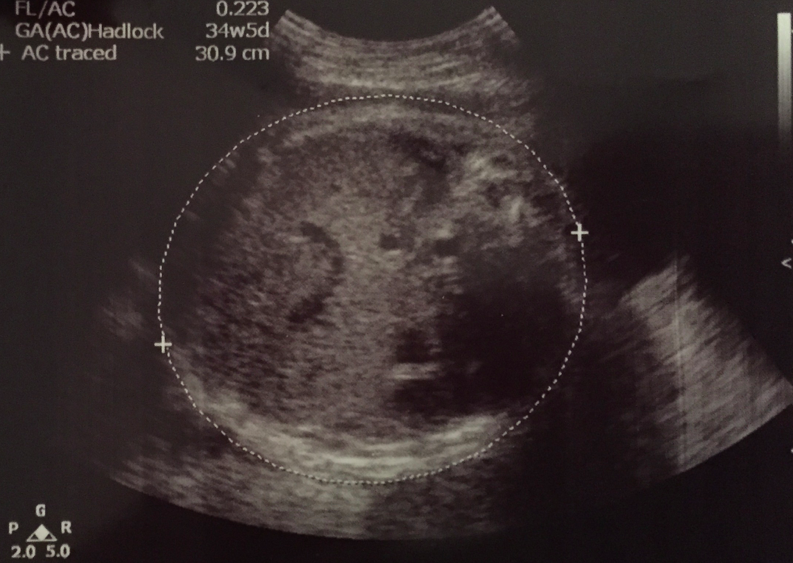

肚仔﹗今日BB呱唔太乖,一直冇吞胎水,所以做唔到完美嘅胃bubble,S醫生不太滿意個plane添,不過佢都話呢個週數度肚仔會相對比較大誤差,媽媽個肚皮面圓圓,所以啲超聲波係左右兩邊唔係penetrate得咁好,變成畫圓嘅線條可能有少少要估,而肚圍係計算胎兒體重嘅formula嘅比重亦比較大,所以個估計體重唔可以盡信囉~